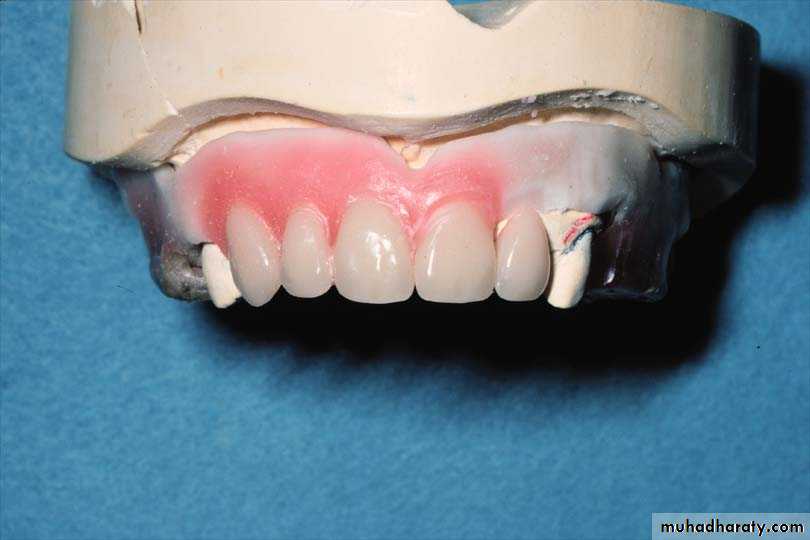

One stone tooth by one is removed and replaced by artificial tooth in the same position; the position of each individual tooth can be more easily copied.

Root sockets are prepared in the stone models into which necks of the artificial teeth are fitted

The labial root portion of the teeth is excavated to approximately I mm on the labial side and flash with the gingival margin on the lingual or palatal side. The depth of the socket should never exceed 5 mm